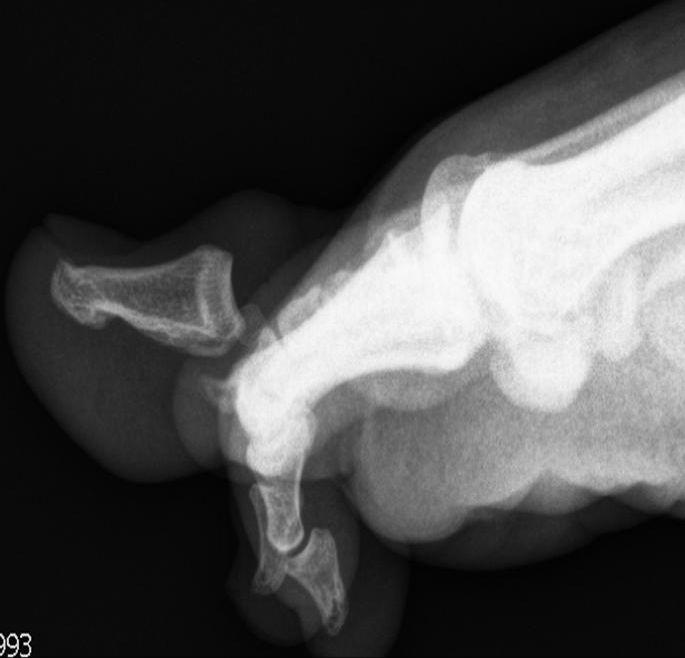

Een 20-jarige student kwam na een trauma naar de Spoedeisende Hulp met een pijnlijke, gezwollen grote teen links met hyperextensie in het interfalangeale gewricht. Gesloten repositie was niet mogelijk. Waarom niet? De laterale röntgenfoto toont de oorzaak.